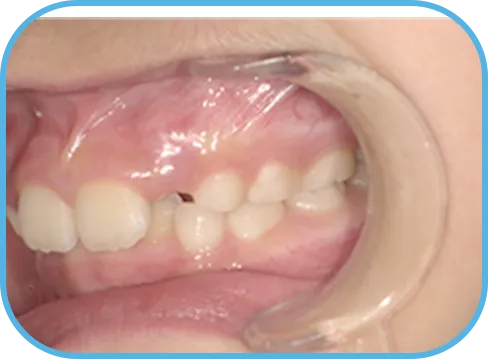

• 右 側

治療前右側からの歯の様子

• 左 側

治療前左側からの歯の様子

主 訴

前歯が開いている

治療内容

インビザライン・ファースト

治療期間

6か月

治療費(税別)

450,000円+診断料30,000円

リスク・副作用

• 親知らずの影響や加齢などによって、凸凹が生じる可能性があります。

• 治療の初期段階では痛みや不快感が生じやすくなりますが、1週間前後で慣れます。

• 顎の成長発育によって、噛み合わせや歯並びが変化する可能性があります。

• 状況により当初予定した治療計画を変更する可能性があります。